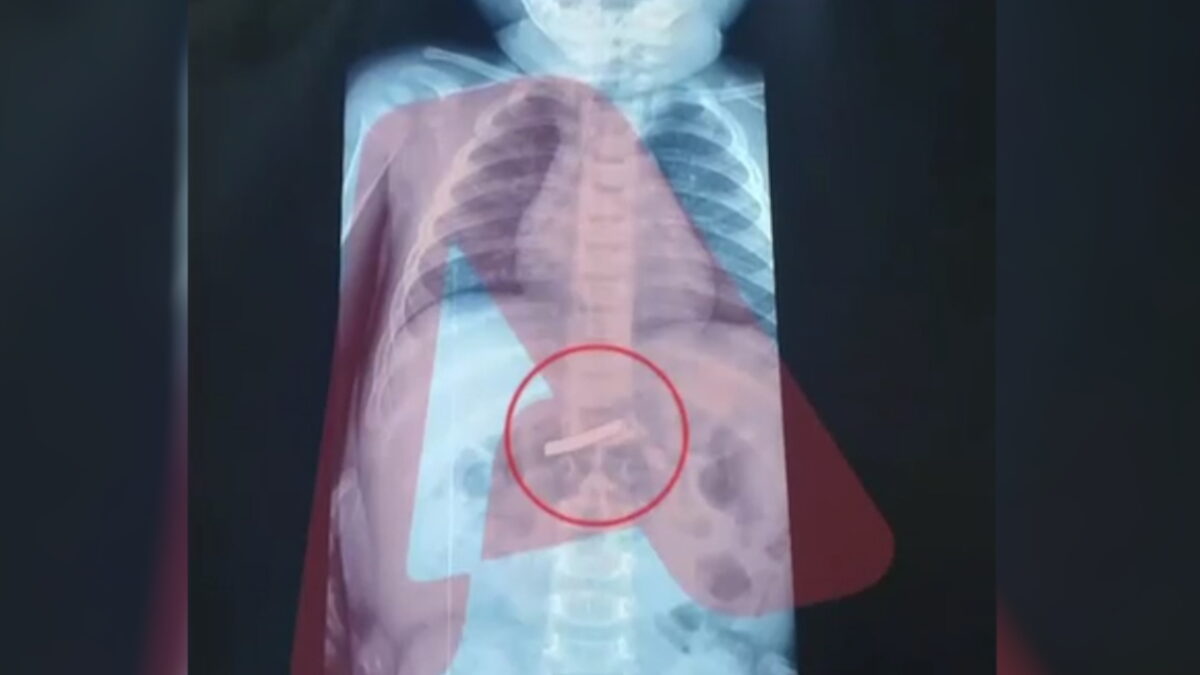

Ένας 3χρονος μεταφέρθηκε εσπευσμένα στο νοσοκομείο, το οποίο κατάπιε ένα ξυραφάκι. Το παιδί αφού έφτασε σε Παίδων της Αθήνας, υποβλήθηκε άμεσα σε ακτινογραφία, η οποία έδειξε ότι όντως υπήρχε το αιχμηρό αντικείμενο στο στομάχι του.

Όπως ενημέρωσαν οι γιατροί, τους γονείς του παιδιού, μετά την ακτινογραφία προσδιορίστηκε και το ακριβές σημείο όπου βρέθηκε το ξυραφάκι, ώστε οι χειρουργοί να προχωρήσουν σε επέμβαση αφαίρεσής του με ασφάλεια.